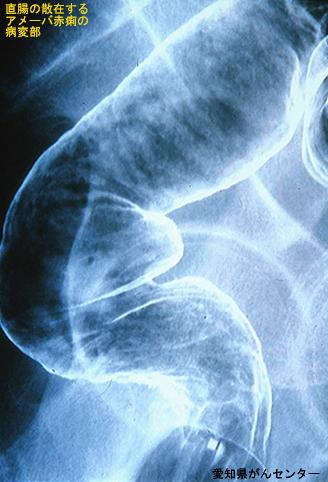

Disentería Amebiana en la que se evidenció Cáncer Precoz de Colon (Caso Conferencia de Tele-Imágenes del Aparato Digestivo combinación de múltiples tópicos --Caso presentado por Centro de Cáncer de la Prefectura de Aichi)

Enfermedad Inflamatoria - Ulcerativa/Disentería Amebiana

colon/recto

Rayos X

20 - 24